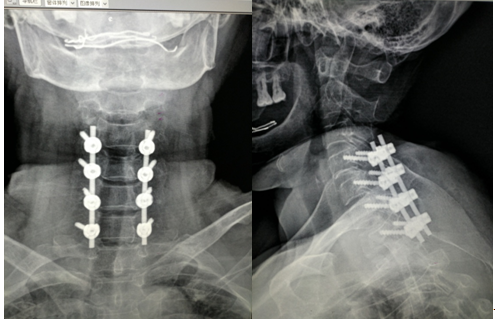

2017年5月,患者張某某因“車禍致頸背部疼痛難忍”入院。入院查體:頸背部、胸背部觸痛、壓痛明顯,雙上肢伸曲肘、腕肌力2級,雙手握力0級。CT及MRI考慮:頸5棘突骨折、頸脊髓損傷伴不全癱、胸椎4-6椎體骨折。

入院后骨科二病區主治醫師張強在汪洋博士及黎圣田副主任醫師的帶領下,仔細的查看病人,積極的為患者制定治療方案。2017年5月9日汪洋博士帶領骨科二病區脊柱團隊在全麻下順利為患者行“頸后路椎管減壓術加側塊螺釘固定術”。

術后經過醫生積極的治療及護士的精心護理,患者順利出院。

近日隨訪見患者恢復良好,雙上肢肌力基本恢復,活動良好?;颊吣樕辖K于露出了久違的笑容。

頸椎手術風險高、難度大,此項手術的順利開展是我科脊柱團隊在開展腰椎微創手術后的又一重大突破,標志著我院骨科二病區對脊柱疾病的處理的水平有了質的飛越。